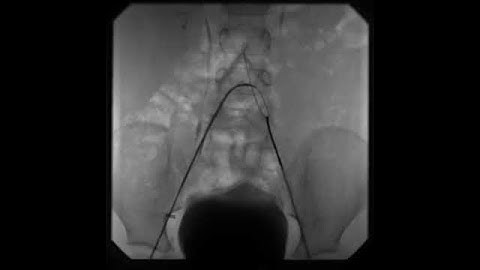

AndraTec Exeter Snare Intravascular Retrieval and Techniques in foreign body retrieval